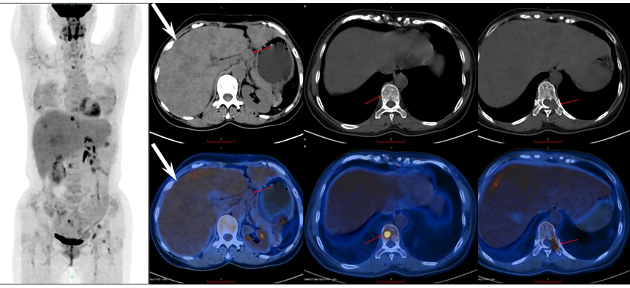

由西安高新醫(yī)院 王淼醫(yī)師 提供

病例(3)為一中年女性,因腹脹就診,實驗室檢查示輕度貧血;增強CT見肝內(nèi)彌漫多發(fā)稍低密度占位病變,增強掃描呈輕度強化;18F-FDG PET/CT示肝內(nèi)病變呈彌漫輕度葡萄糖代謝增高,全身多發(fā)骨質(zhì)破壞伴代謝增高;肝穿刺病理提示上皮樣血管內(nèi)皮瘤(Epithelioid hemangioendothelioma,EHE)。